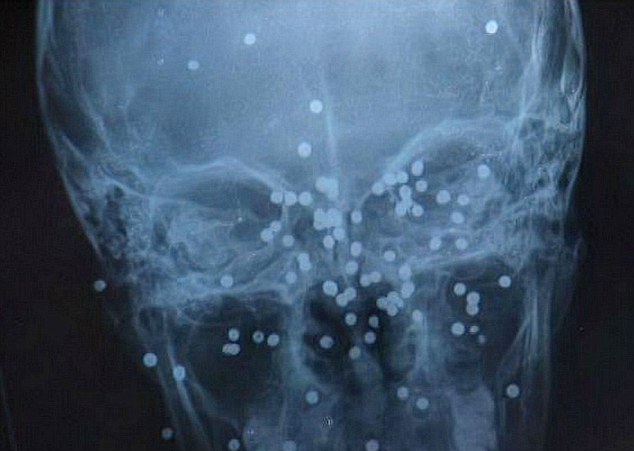

Το περιστατικό συνέβη πριν από τρεις μήνες. Η Zhang τυφλώθηκε από το ένα μάτι, ενώ το πρόσωπό της γέμισε σημάδια από τα 68 μικρά μεταλλικά κομμάτια που εμφυτεύτηκαν στην κυριολεξία μέσα σε αυτό.

Ο πατέρας της απευθύνθηκε σε αρκετά νοσοκομεία, όμως όλα αρνήθηκαν να μπουν στη διαδικασία να αφαιρέσουν τα μεταλλικά θραύσματα επειδή θα ήταν επικίνδυνο για την υγεία της Zhang.